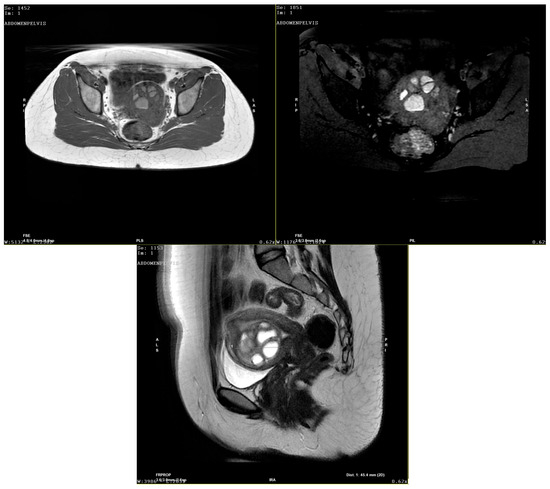

It is with great pleasure that I invite you to submit articles for the “Interesting images” Special Collection. Since we introduced Interesting Images as an article type in Diagnostics, it has served as a valuable resource for the imaging community. Many have relayed that they use these image-based case reports when encountering challenging cases or images of diseases rarely seen. Further, pitfalls are covered by this type of article and may be helpful both for experienced and less experienced image readers in making a correct evaluation.

The interesting Images together serve as a live imaging atlas covering PET, CT, MRI, and other imaging modalities. Therefore, the more cases we publish, the more likely it is that image interpreters with a difficult case can be supported by previously published cases. Although focus until now has largely been on clinical cases, it should be noted that nonclinical cases are also welcome, e.g., from preclinical in vivo imaging, including optical imaging as well as histology images from pathology.